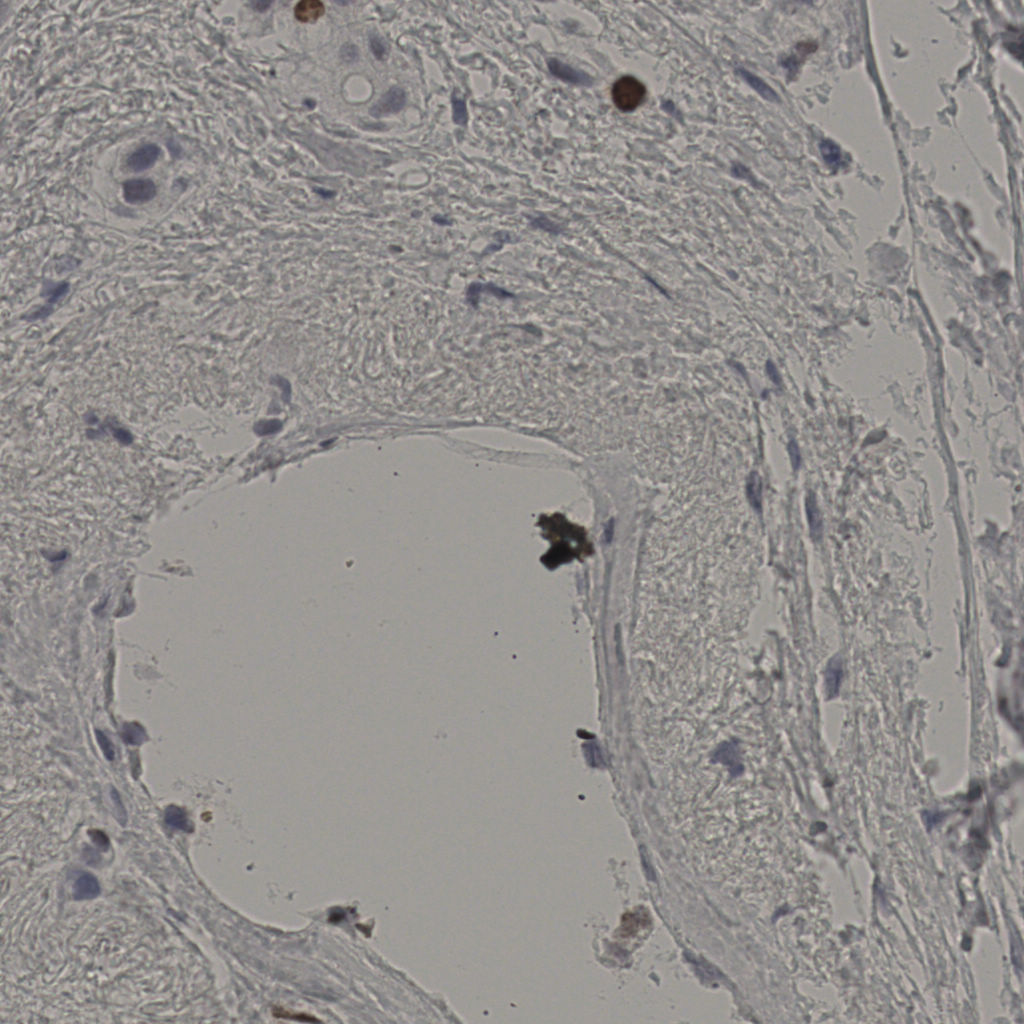

缩略图

标记后

标记前